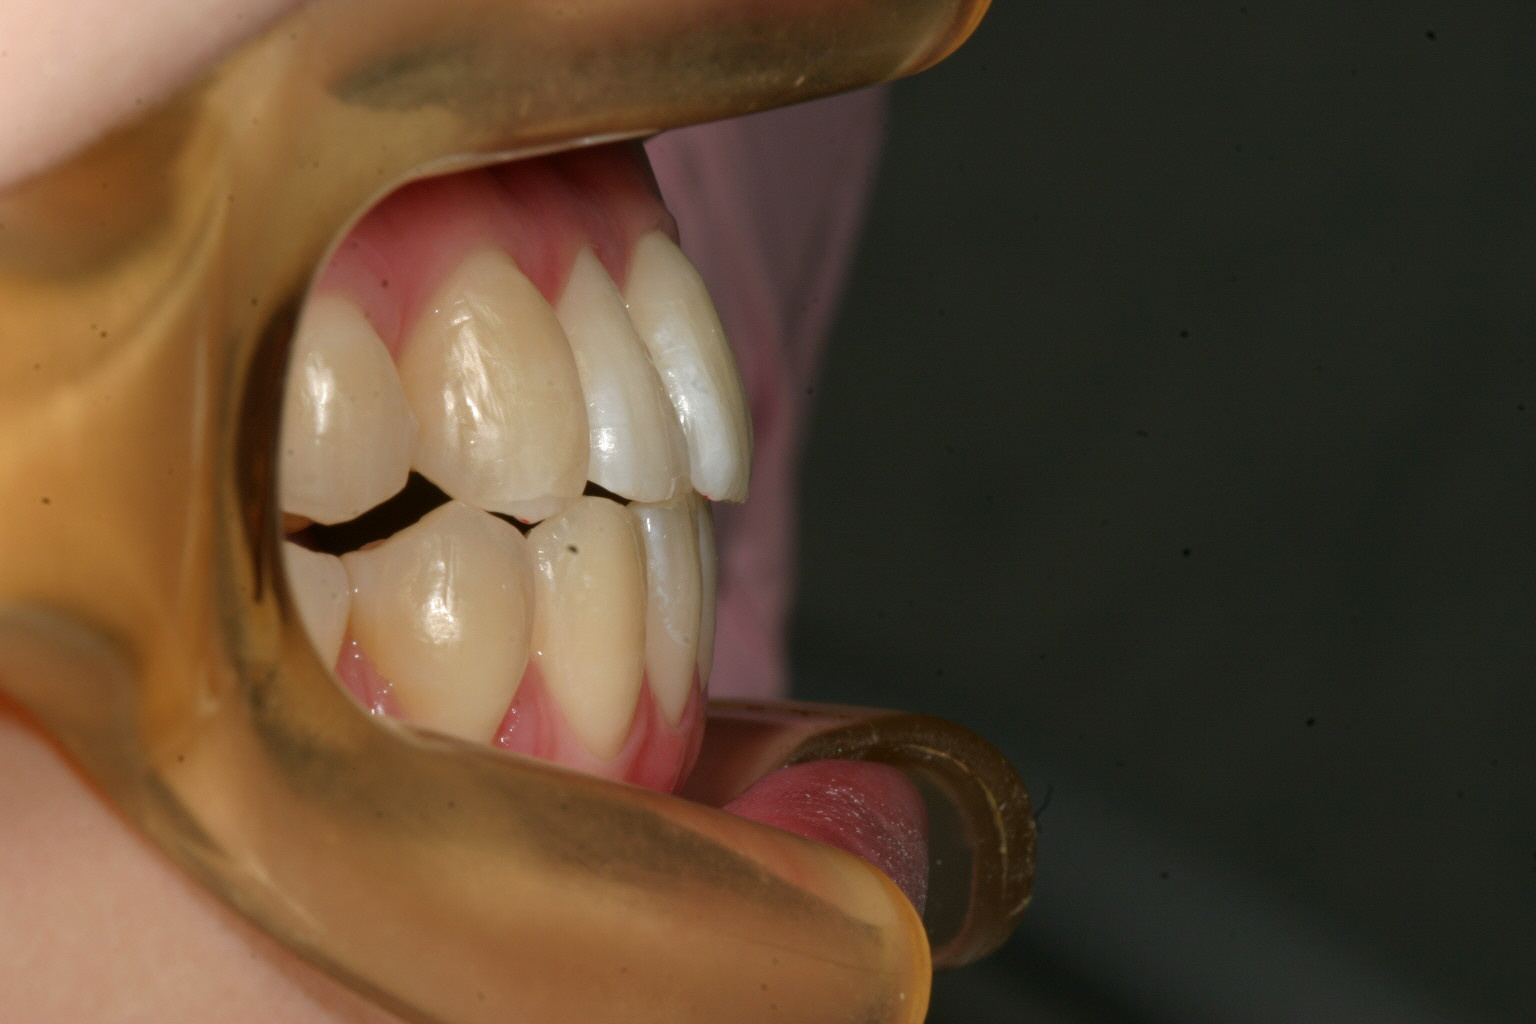

綺麗に改善出来ています。

オーバージェット感も問題ないです。

今回の様なケースは見た目は大変そうに見えるのですが治療してみるとそうでも有りませんよ!